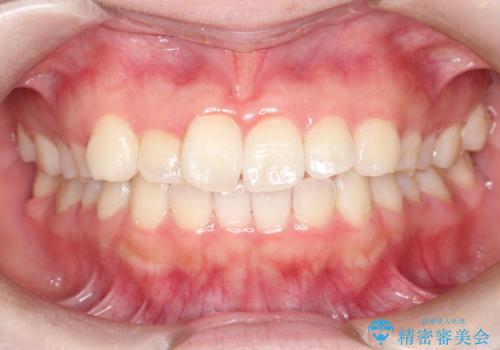

一度諦めた矯正にチャレンジしたい インビザラインとセラミック治療

少しだけ飛び出た前歯を整えたい インビザラインによる矯正治療

抜けてしまうと言われた前歯 インビザラインによる矯正治療

深いかみ合わせ 出っ歯の治療 インビザラインで

見た目だけじゃない:マウスピースでも短期間で噛み合わせと口元を改善

飛び出した前歯と黄ばんだ歯 ホワイトニングしながらマウスピース矯正

下の前歯が見えない:深い噛み合わせもインビザラインで

【モニター】前歯のデコボコをインビザラインできれいに整える

治療途中の前歯を治したい インビザライン矯正とオールセラミッククラウン

入国制限で帰国できず 海外出張中のインビザライン矯正

前歯のデコボコと突出感 インビザラインにて矯正治療

奥歯の銀歯と歯並びを改善 歯周外科治療と矯正治療を行った総合歯科診療

マウスピース矯正の注意事項(リスク・副作用など)

- 口腔内・歯並びの状態によっては対応できない場合があります

- マウスピース型矯正装置の長時間装着が必須です

- 治療計画通りに進めるためには、患者様の意志が重要になります

- 矯正治療後の保定が不十分だと後戻り(元の位置に戻ろうとする動き)をします

- 自費診療(保険適用外)となります